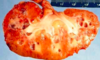

What do you see here?

Acute interstitial nephritis

What is the clinical presentation of AIN?

- Usually w/in 3 weeks of starting the new drug (or temporarily related to an infection)

- Sudden onset of renal insufficiency

- Fever, Rash, flank pain, hematuria, sterile pyuria (urine w/WBCs, pus), eosinophiluria

1. Bulk of WBC’s will be neutrophils - Minimal proteinuria -> glomerulus is fine